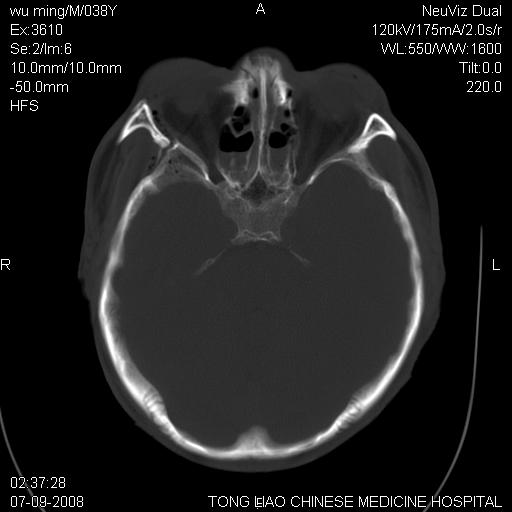

颅底多发骨折。

颅底多发骨折.

颅底多发骨折.上颌骨多发骨折

右侧眼眶,上颌骨,鼻骨、上颌窦等很多

1)颅底骨及颌面骨多发性骨折。2)副鼻窦及双侧鼻腔积血。

颅底骨折,窦腔内积血。考虑死亡原因为脑水肿压迫脑干或因大量失血死亡。

前颅窝颅底骨折,死的原因应该从头部来看不用说就是重度颅脑损伤。